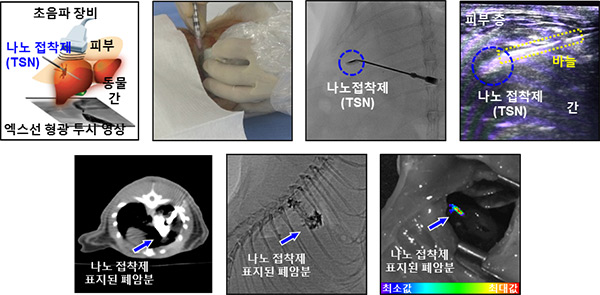

▲ [그림 4] 동물실험에 나노 접착제를 적용해 영상기반 시술 구현. 토끼 간의 내출혈 지혈(상단 좌측부터 실험과정 시술 사진, 엑스선 투시, 초음파 영상), 폐암에 걸린 실험쥐의 폐암조직 표지(하단, 컴퓨터 단층촬영, 엑스선 투시, 형광 영상).